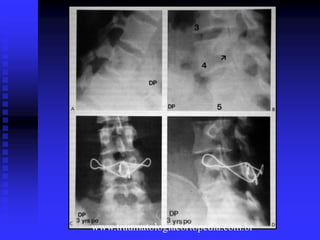

Tratamento da Espondilólise 2.Tto cirúrgico: sem melhora ao tto conservador. . Artrodese póstero-lateral lombossacral L5- S1. . Reparo do defeito: defeitos na pars de L4 ou mais alto, fixação com fios de aço, fixação com parafuso através da fratura da pars, fusão lombossacral com enxerto.

Tratamento da Espondilolistese 2.Cirúrgico: sintomas persistentes sem melhora ao tto conservador ou deslizamento maior que 30 a 50% mesmo se assintomático. . Artrodese póstero-lateral de L5-S1 ou extensão para L4 em deslizamentos de 50% ou mais; . Fusão anterior: graus mais graves; . Descompressão em casos de fraqueza motora ou déficit neurológico; . Redução: deslizamentos maiores que 25% ou presença de instabilidade.

Redução da Espondilolistese Objetivos: evitar a progressão, aliviar a dor, reverter déficit neurológico, melhorar a função.  Graus maiores que 25% ou presença de instabilidade.  Por meio de técnicas de engessamento, por implantes posteriores, abordagens combinadas ( grave dor + deficiência importante, % de deslizamento > 75 a 80% e â de deslizamento > 45º, maturidade esquelética, deformidade rígida com perda do alinhamento sagital).

 Uma técnicaalternativa de redução consiste de ressecção de L5.  É importante lembrar que a principal causa da deformidade é a cifose lombossacral, e não a % de deslizamento.